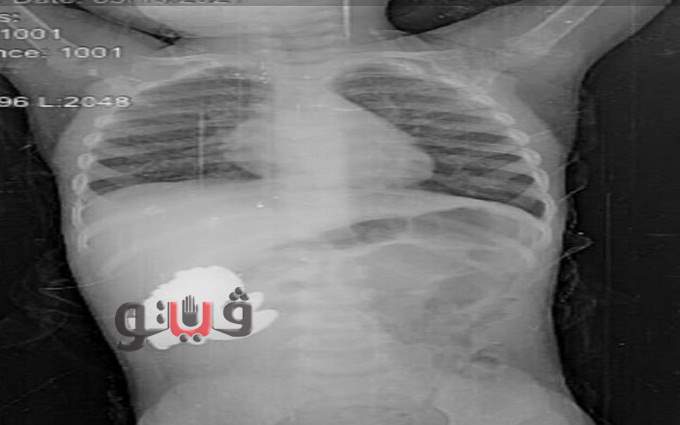

كانت والدة الطفلة اصطحبتها للقسم في حالة يرثى لها تشكو من معاناتها بالقئ والآم في البطن منذ ما يقرب من الأسبوع ليهرع بها الأطباء وعمل عدة أشعات تبين وجود جسم غريب داخل البطن فقرروا إخضاعها إلى عملية جراحيه عاجلة.

تشكل الفريق الطبي من قسم جراحة الأطفال برئاسة الدكتور أحمد عزت رئيس القسم وفريق من قسم التخدير، ليتفاجئوا بوجود ما يقرب من 30 قطعة معدنية داخل أحشائها عبارة عن صواميل ومغناطيس.

وهي ما تسببت في حالة القيء والإعياء الشديد التي عانت منهم الطفلة على مدار أيام وتم استخراج القطع بنجاح، فيما أفادت الأم بأن الطفلة تلهو في الشارع بالقرب من إحدى الورش وربما ابتلعت هذه القطع أثناء ذلك.